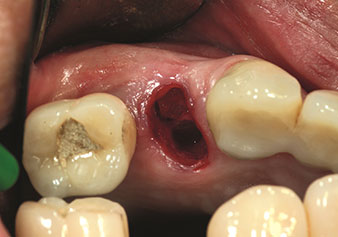

Preparazione della sede dell’impianto con lo strumento I4P

Fig. 3: Preparazione della sede dell’impianto con lo strumento I4P.

Dopo la preparazione dei seni mascellari con il corrispondente set di strumenti (Fig. 3), il nuovo strumento Z35P (Fig. 4) viene utilizzato per sollevare la membrana idrodinamicamente. Lo stesso set di strumenti può essere utilizzato anche per la preparazione piezochirurgica della sede dell’impianto in diametri crescenti (Figure 3 e 4 inserite grazie alla gentile concessione del Dott. Mario Kirste, Frankfurt/Oder).